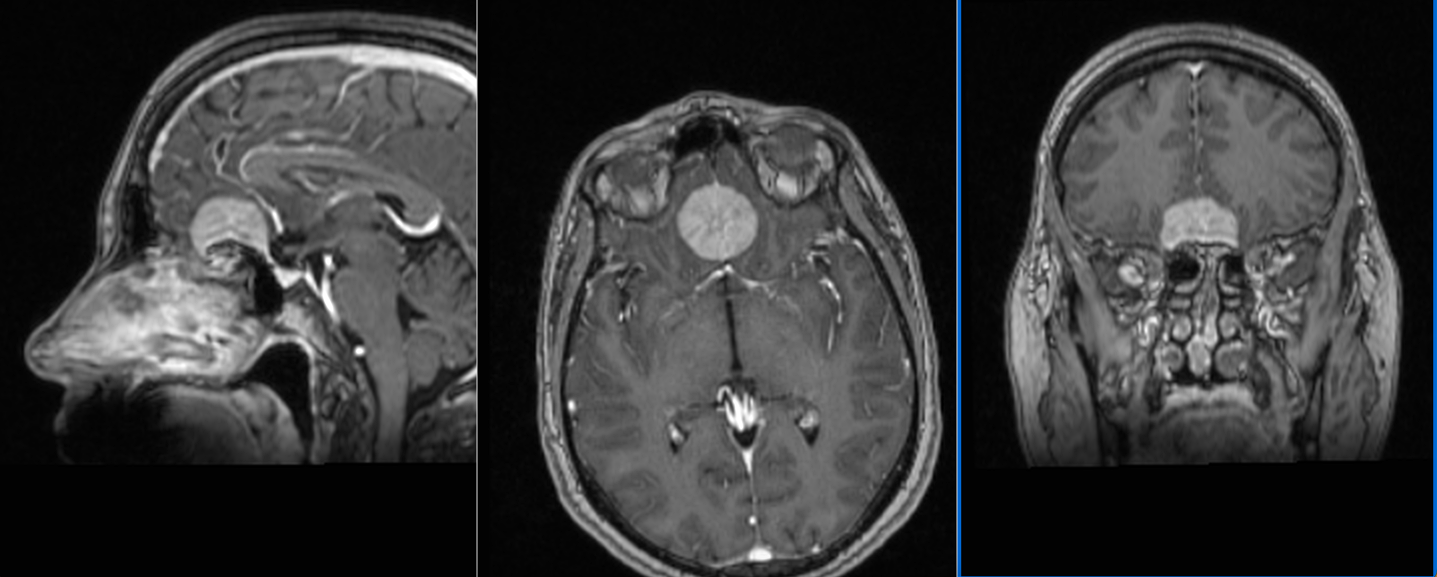

Tumora era bine delimitată, cu priză omogenă de contrast, și are origine din dura mater (foița externă a meningelui) de la nivelul șanțurilor olfactive – porțiunea din baza craniului pe unde trec nervii olfactivi. Aspectul RMN sugerează un diagnostic histopatologic de meningiom – tumoră benignă (în peste 95% din cazuri) .

Intervenția chirurgicală este cea mai bună soluție în asemenea situații, pentru că, deși benignă, tumora va continua să crească și va începe să determine și alte manifestări neurologice (crize comițiale, afectare vizuală, declin cognitiv – demență, etc.). De asemenea, cu cât tumor este mai mare, cu atât mai lungă și dificilă va fi operația, în timp ce pacientul va fi mai vârstnic și, posibil, cu mai multe suferințe cronice asociate. Un aspect care merită menționat este că portiunea posterioară a tumorii ajunge în apropierea celor doi nervi optici, fără a-i comprima (încă!).